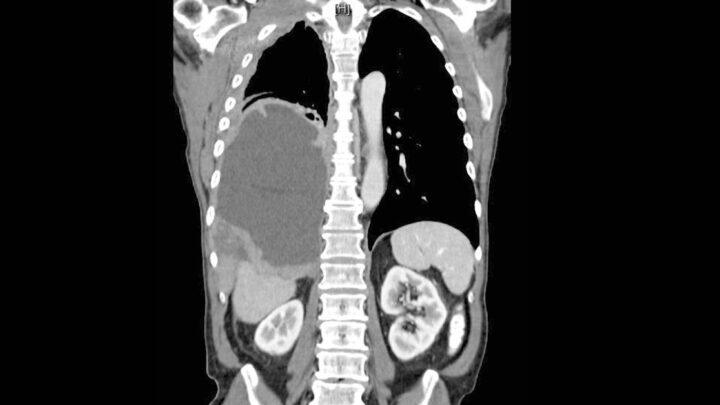

Mesotelioma

O mesotelioma é um tumor incomum decorrente do revestimento mesotelial de cavidades serosas. É mais freqüentemente na cavidade pleural (cobertura…